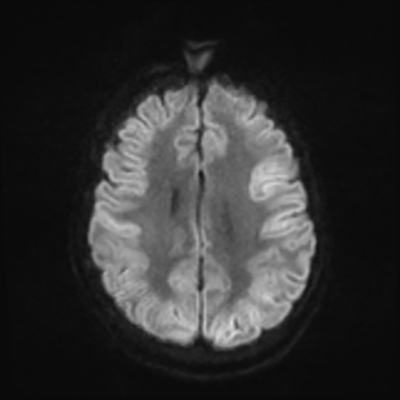

MRI brain (DWI)

MRI brain (DWI) 1/24 1/24

You can clearly see diffuse cortical and basal ganglia diffusion restriction, and that of his deep cerebellar nuclei as well. The right occipital lobe abnormalities are a little more prominent, but then you remember that he is known to have had a right occipital stroke weeks ago.

In reviewing his data, you know that he doesn't have any of the strong predictors of a poor neurologic prognosis. However, based on these findings on MRI, along with the absent reactivity on cEEG, you are able to tell the primary team and the patient's family that he is likely to have a poor prognosis, based on these multiple moderate predictors. Recovery is not completely impossible-- there is more uncertainty with this prognostication than if we were able to get SSEPs-- but you're very worried about his outlook and that any potential recovery would require a very protracted rehabilitation period. Given his high cervical cord injury level, tracheostomy would be required anyway. So, it comes down to whether his family thinks he'd want to pursue these aggressive measures.